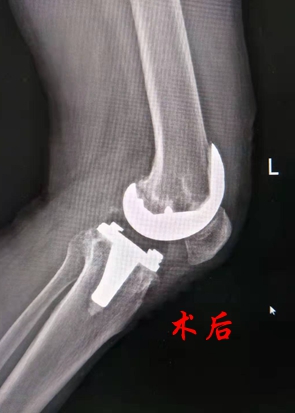

术前,关节科团队为黄大伯详细做了检查。因黄大伯同时伴有心脏病、胃病、酒精肝,为保证手术顺利进行,关节科邀请综合内科、手术室、麻醉科等科室联合会诊,进行术前综合评估,并制订了详细的手术和术后恢复方案。3天后,刘卓华院长带领关节科专业团队为黄大伯实施了左侧人工膝关节置换术。该患者由于病程长、关节磨损严重,内侧平台骨缺损严重,因此手术最大的难点是要求操作精细,历经1个半小时,手术顺利完成。术后黄老伯生命体征平稳,第二天在专业康复师的指导下借助助行器行走。

人工膝关节置换术是用人工假体取代已严重损坏而不能行使正常功能的膝关节表面,该手术适用于膝关节骨性关节炎、类风湿性关节炎、创伤性关节炎、骨缺血坏死或肿瘤等病变所致的严重疼痛和(或)功能障碍,能非常有效地缓解晚期膝关节病痛,改善膝关节功能,纠正膝关节畸形,极大地改善病人的生活质量,它是目前膝关节疾病最佳的治疗方法。